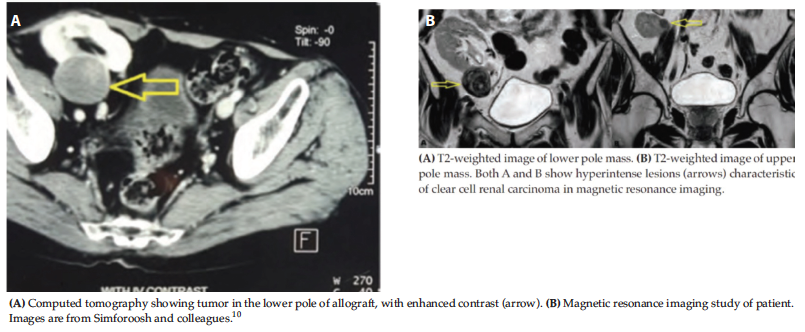

Zero-Ischemia Partial Nephrectomy for Treatment of Multifocal Renal Cell

Carcinoma

Traditionally, if renal cell carcinoma is discovered in the transplanted kidney,

radical nephrectomy is recommended, especially if there is more than 1 tumor. As

shown in Figure 6, we were able to spare a transplanted kidney with 2 tumors (1

in the upper pole and 1 in the lower pole). This was possible with use of the

enucleating technique on the tumor (without invading the tumor capsule) instead

of the popular partial nephrectomy. We did not clamp the renal vessels, thus

avoiding induced ischemia in the transplanted kidney.10

Figure 6. Imaging of Renal Cell Carcinoma